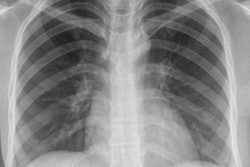

Dutch researchers have developed an algorithm to improve the robustness of computer-aided detection (CAD) to identify tuberculosis (TB) on chest x-rays -- enabling CAD to significantly improve the detection of thoracic abnormalities.

Rick Philipsen from Radboud University Medical Center.The team from Radboud University Medical Center in Nijmegen applied an algorithm called an energy normalization process to standardize the appearance of chest radiographs. In their study, the researchers combined the technique with an existing TB CAD scheme to reduce energy variations in 600 radiographs from different x-ray units, allowing CAD to improve the identification of patients with tuberculosis.

The performance of CAD systems used in chest radiography can be influenced by several kinds of variations in image data that typically come from different sources, Philipsen said. Different detector technologies, different acquisition settings, proprietary postprocessing techniques, and other factors can all influence the appearance of radiographs, reducing the accuracy of CAD algorithms.